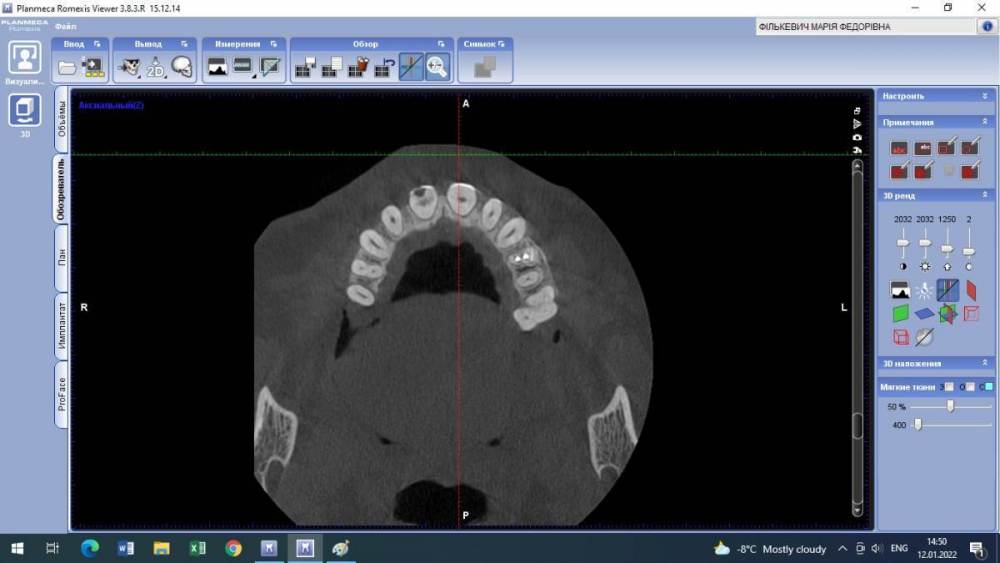

Lyubanya Опубликовано 12 января, 2022 Поделиться Опубликовано 12 января, 2022 Здравствуйте, коллеги. Вот такой случай. 11 зуб, пациентка 1963 г.р. Найдено случайно на КТ, делала его 3.09.21 по другому поводу, я взяла посмотреть для эндо премоляров. Визуально во рту вижу легкую розоватость пришеечно, и есть место, где цепляет зонд. Вопросов много. Каков точный диагноз? И что делать с этим зубом? Есть ли у него шансы пожить еще? Я так понимаю по возможности делается эндо в таком зубе. Если есть шансы то какова тактика? Ссылка на комментарий

Lyubanya Опубликовано 15 января, 2022 Автор Поделиться Опубликовано 15 января, 2022 9 часов назад, Александр23712 сказал: @Lyubanya Лично я бы, если не беспокоит, пока не трогал, но пациентку бы предупредил и кт показал. Может она ничего и не поймет, зато, когда/если заболит, придет к вам. Процесс прямо чуть ниже шейки. Как я понимаю, чтобы такое лечить, вам надо сначала лоскут откинуть, дальше в зависимости от кортикальной пластинки. Но у композита к дентину спорная адгезия ? . По поводу эндо не представляю, зачем депульпировать зуб раньше срока. Сделайте прицельный еще в 2 проекциях, интересно посмотреть Какая конкретно это резорбция? Разряжение вокруг основного канала = внутренняя резорбция корня? Или нет? Просто пыталась найти инфо, и нашла что внутренние это эндо. Но если можно наблюдать, то я только за) Пациентка работает у нас санитарочкой и я совсем не хочу ей лишнего стресса и тем более потери зуба. Хотела с главврачом обсудить, но пожалуй пока не буду. У меня на КТ нашлось новообразование, он ходил давил что надо удалить зуб вместе с ним. В итоге спустя полгода оказалось, что это цементно-костная дисплазия и ничего удалять не нужно. Спасибо Рогацкину.? И как мне сделать две проекции на пленочном?? 9 часов назад, Дмитрий Л. сказал: Реставрация без эндо; риск рецессии. Имеете ввиду перекрыть то место, где зонд цепляется? Ссылка на комментарий

Дмитрий Л. Опубликовано 15 января, 2022 Поделиться Опубликовано 15 января, 2022 Это инвазивная цервикальная резорбция, связи с пульпой нету, хирургически можно откинуть лоскут и реставрировать. Риск рецессии. Другое лечение - выжидание, риски прогресса с потерей зуба, смотрите на возраст пациента. 1 Ссылка на комментарий

Lyubanya Опубликовано 16 января, 2022 Автор Поделиться Опубликовано 16 января, 2022 8 часов назад, Дмитрий Л. сказал: Это инвазивная цервикальная резорбция, связи с пульпой нету, хирургически можно откинуть лоскут и реставрировать. Риск рецессии. Другое лечение - выжидание, риски прогресса с потерей зуба, смотрите на возраст пациента. А вот размытость дентина вокруг хода канала, это она же? Думала насчет лоскута, но я так понимаю поможет он не особо, там альвеола уже.? Ссылка на комментарий